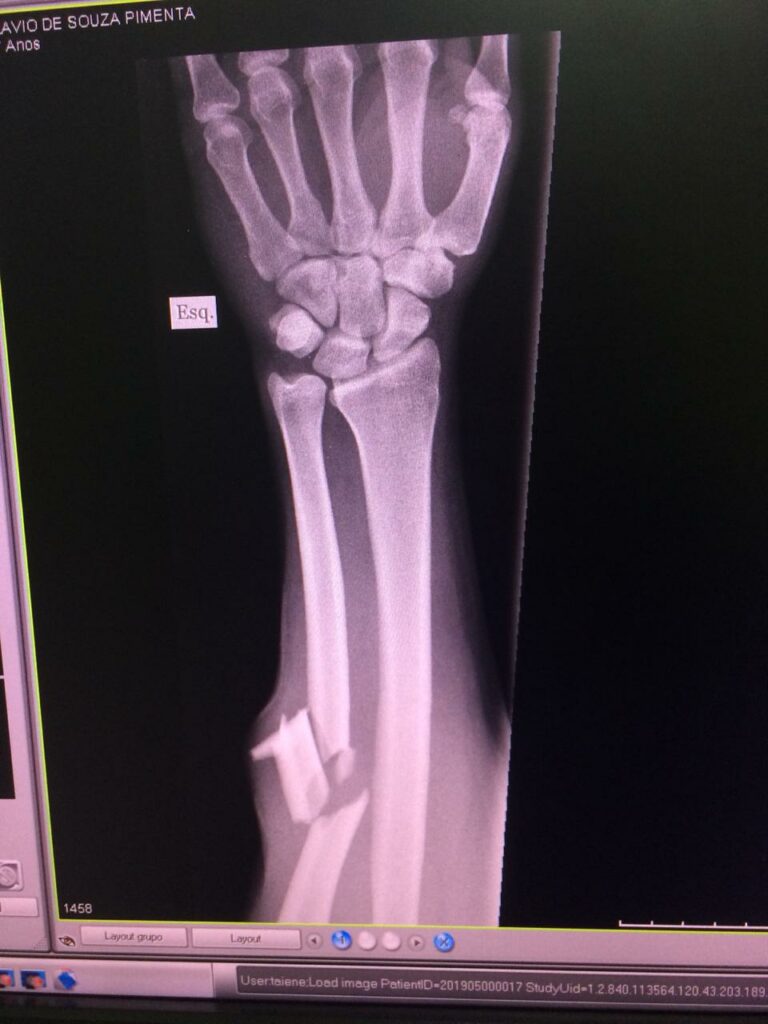

A queda de um galho de árvore de grande porte deixou um ferido e danificou dois veículos, no interior de uma propriedade rural, na tarde da última quarta-feira (08), nas proximidades do bairro Morro da Formiga, Natividade. No momento do incidente, algumas pessoas estavam no local – Sítio Boa Vista – e o genro da proprietária, Flávio de Souza Pimenta, de 47 anos, acabou atingido no braço, que sofreu fratura. Ele foi socorrido ao pronto socorro do Hospital Natividade e transferido ao São José do Avaí, em Itaperuna, onde aguarda realização de cirurgia ortopédica.